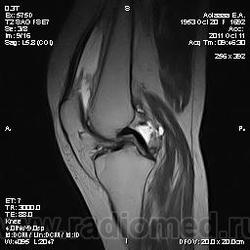

Дискуссия о природе "структры" в проекции передней поврехности метадиафиза бедренной кости.

Две версии: А. костно-хрящевой экзостоз. Б. разрастания сумки.

Пациента на МРТ прислали с травмой. "Это" было выявлено в ряду другой патологии как случайная находка. Рентген не было возможности сделать - дистанционная диагностика. Хотя это конечно была первая мысль. Спасибо за внимание к посту.

За надколенником по передней поверхности бедренной кости на МРТ и РКТ (наверное не так наглядно) - костно-хрящевой экзостоз.

Уважаемый коллега, nnemo, большое спасибо, за уточнение, что Вы подразумеваете именно костно-хрящевой экзостоз, т.е остеохондрому. Где Вы его подразумеваете я, вобщем-то, догадалась. Однако, я спрашивала и просила показать на МРТ: на основании каких семиотических признаков Вы сделали заключение, что это именно остеохондрома, а не какая-то другая патология?

"самоуверенность дилетантов - предмет зависти профессионалов"

tatyana, Вы в чем то правы. Складывается впечатление что кортикальная пластинка бедренной кости почти не изменена (или не изменена вовсе). Поэтому и были сомнения. Кроме того можно отметить, что вся синовиальная оболочка бурсы тотально утолщена, что тоже наводила на определенные соменения. Наверное изменение кортикальной пластинки, которые абсолютно четко увяжут заключение с костно-хрящевым экзостозом, можно указать с "натяжкой". Скорее это волевое решение в пользу костно-хрящевого экзостоза. Еще были мнения "вилонодулярном синовиите", а также "хондроматозе". Так что возможны варианты.

Чевой то мне, паростальную напоминает.

Неужели не похоже на экзостоз?!

Преклоняюсь перед людьми, которые по таким рентгенграммам выставляют точный морфологический диагноз. Это практически режим Бога (God mode), как говорят в компьютерных играх. Тенденцию к комплексу неполноценности можно развить в ком угодно (и Вам это почти удалось). По моему "это" широко прилежит или даже правильнее сказать исходит из кости. При этом несколько утолщая кортикальную пластинку и суживая костно-мозговой канал на этом уровне. Если заключение лежит в плоскости текущего поста, то я бы больше склонился к костно-хрящевому экзостозу, хотя тут диф ряд может проистекать от оссифицированной гематомы до неопроцесса.

P.S. Я показала паростальную остеосаркому, как сходу и написал Валентин Львович ))))